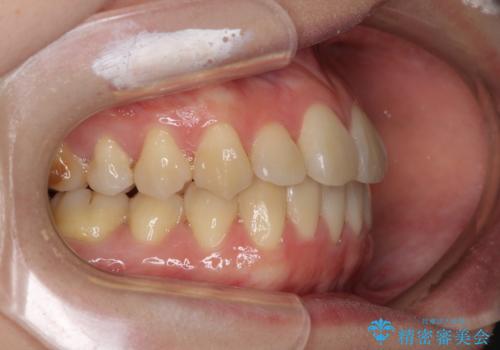

- 前歯の反対咬合を気にして来院された患者様です。

目立ちにくい装置での治療をご希望とのことで、上顎が裏側装置、下顎が表側装置のハーフリンガルにより矯正治療を行うこととしました。